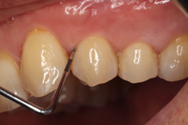

Before

初診時歯周ポケット6mm、左上4番に骨吸収を認める

切開はEPPT(entire papilla preservation technique)